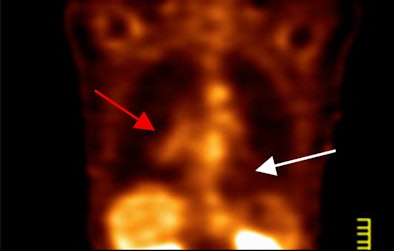

| PET scan, above, indicates the presence of a large tumor (red arrow); the corresponding ECDG-SPECT image, below, also defines the presence of the mass (red arrow). The FDG-PET image also shows benign pulmonary nodules (white arrow), which are not see on the ECDG-SPECT image, indicating they are not representative of cancer. Images courtesy of F. David Rollo, MD, PhD, and Cell>Point. |

The study found that ECDG-SPECT matched FDG-PET in image interpretation for all primary lesions. With FDG-PET, the researchers wrote, primary lesions had a "fluffy appearance and were larger than noted on pretreatment PET, consistent with chemotherapy inflammatory response. For SPECT, the primary lesions were smaller and more discrete, consistent with clinical findings of chemotherapy efficacy."